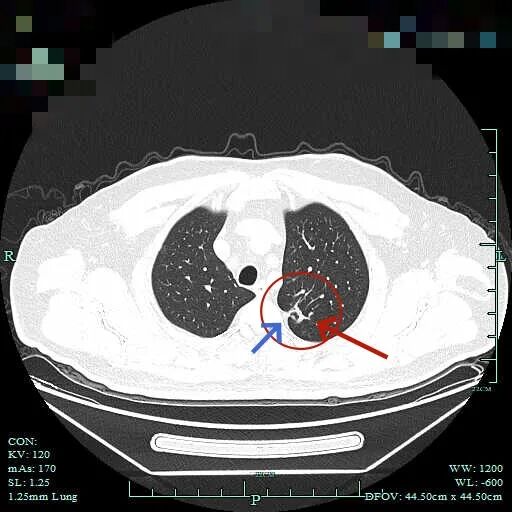

再看2025年10月时该市级中医院的影像:

病灶到了2025年10月范围略有扩大,但不太厉害,不过密度明显增加,表面不平,整体轮廓与瘤肺边界清楚,灶内有条状密度增高,靠右侧向叶间裂处延伸,已经搭上胸膜了。这基本上就是浸润性癌的了!